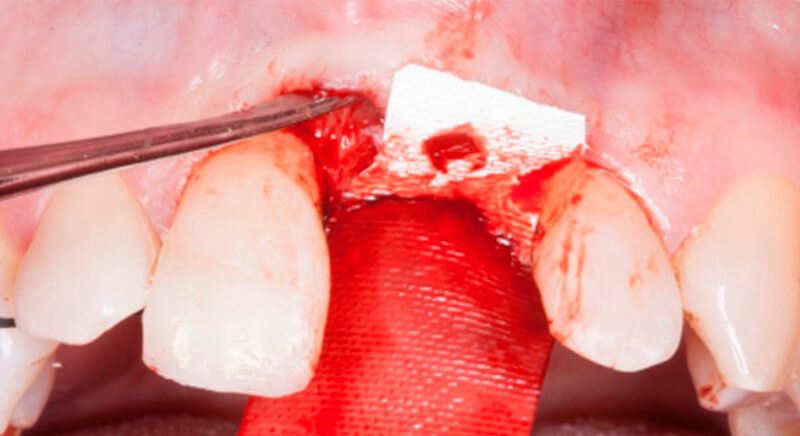

The socket was filled with a xenograft after the extraction and a graft of connective tissue was placed in the vestibular area of the two upper central incisors.

The tissue with epithelium was taken from the palate and de-epithelialized outside of the mouth. This obtains a lamina propria graft with better density and quality than if it were obtained with a single incision to the palate.

The guided surgery was performed by lifting a full thickness mucoperiosteal flap. A Biomimetic Ocean CC implant, diameter 3.5mm and length 10mm, was inserted using the surgical guide in the ideal three-dimensional position and the defects were regenerated with xenograft and reabsorbable membrane, the nasopalatine duct on the palatine side and the area of dehiscence on the vestibular.